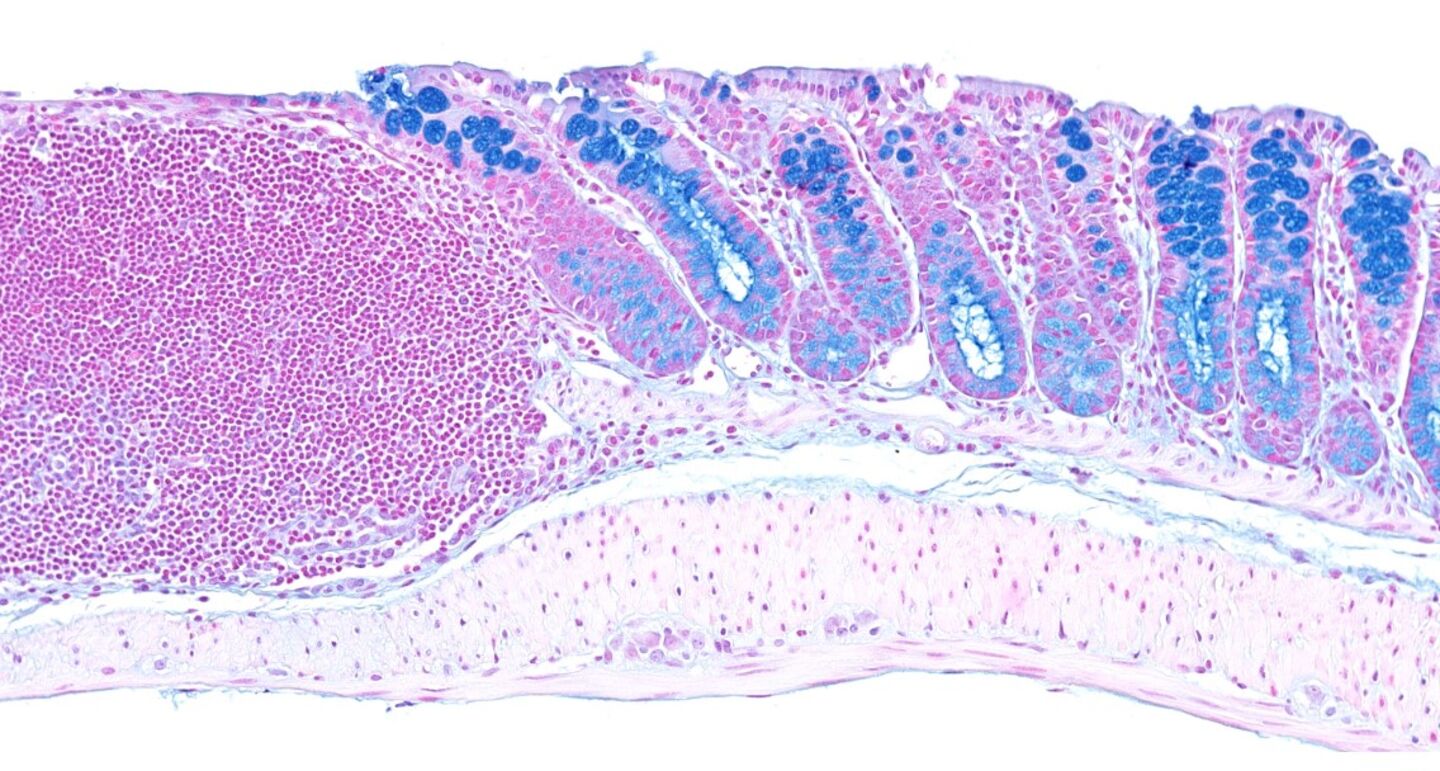

Färgning med Alcian Blue/Neutralrött av den distala delen av musens tjocktarm. Mucinet i bägarcellerna (gobletceller) är blåfärgat. Ett stort lymfoidaggregat kan ses till vänster.